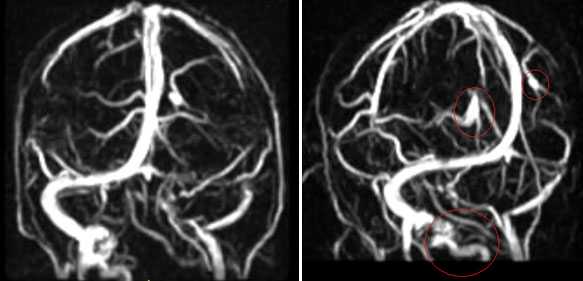

Исключали клинически значимую кардиологическую и лёгочную патологию. Обработку полученных данных проводили при помощи пакета статистических программ SPSS 10 с использованием критериев Стьюдента и Манна - Уитни. Результаты и их обсуждение. Учёт венозной фазы кровотока при МРТ-реконструкции сосудов головного мозга позволил верифицировать варианты развития поперечного и сигмовидного венозных синусов в виде их гипоплазии (рис.1) и полной аплазии (рис. 2).

Рис. 1. МРТ-визуализация сосудов головного мозга с венозной фазой мозгового кровотока. Гипоплазия левого сигмовидного и поперечного венозных синусов головного мозга. Существенное снижение кровотока в левых сигмовидном и поперечном синусах. Асимметрия кровотока в яремных венах - 86 и 14 %

Рис. 2. МРТ-визуализация сосудов головного мозга с венозной фазой мозгового кровотока. Отсутствует кровоток в левых сигмовидном и поперечном синусах. Асимметрия кровотока в яремных венах - 98 и 2 % (аплазия синусов)

МР-венография - отсутствие визуализации кровотока в правом поперечном синусе и яремной вене.

МР-венография: тромбоз левого поперечного синуса. Отмечается потеря МР-сигнала от левого поперечного синуса.

МР-венография: тромбоз правого поперечного синуса. Отмечается потеря МР-сигнала от правого поперечного синуса.

МРА-картина выраженной асимметрии венозной сети с преобладанием и нерезкой дилатацией вен правой гемисферы (поперечного, сигмовидного синусов и яремной вены справа); гипоплазии левого поперечного и сигмовидного синуса. Единичные участки (2) локального расширения вен в парасагиттальных отделах левой гемисферы, большой вены мозга. Асимметричная, расширенная и выражено извитая венозная структура экстракраниальных отделов справа.